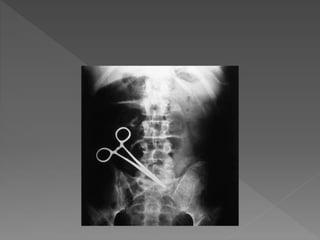

An article inthe Gurdian newspaper UK in March 2013 claimed that “five worst medical” nightmares a Pt faces, three related to surgery: 1. Wrong site surgery 2. Wrong patient surgery 3. Retained instruments and swabs The rate of harm in surgical patient is unknown but probably occur in about 10% surgical patient, though much of this harm will be minor.

1. Wrong patientin the operation theatre. 2. Surgery performed in the wrong side or site 3. Wrong procedure 4. Failure to communicate changes in the patient condition. 5. Disagreement about proceeding. 6. Retained instruments or swabs.